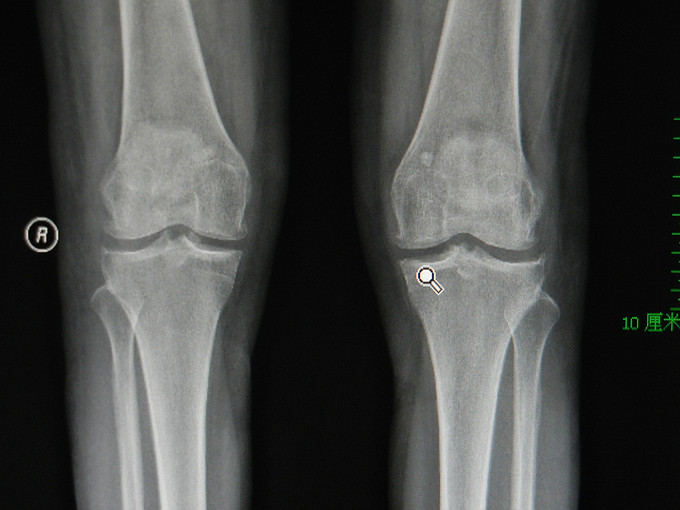

患者女,53岁。因“双膝疼痛3周”入院。现病史:患者于3周前无明显诱因出现双膝关节疼痛不适,以左膝为主,上下楼及下蹲时疼痛明显加重,于当地医院就诊行拍片及“血沉”,“RF”及“ASO”检查后专至我院,门诊检查双膝MRI示“双膝OA:双膝游离体“诊断收住院。患病以来患者一般情况良好。 既往:乳腺增生手术史10余年。

查体:生命体征平稳,心肺腹体检未见明显异常。专科情况:双膝略显肿胀,压痛可疑阳性,过伸过屈阳性,浮髌试验可疑阳性,双膝内外侧方实验阴性,抽屉实验可疑阳性,双下肢远端血循环、运动和感觉可。 检查:双膝OA,滑膜炎,腘窝多个小滑膜囊肿形成。

诊断:1、双膝游离体。2、双膝OA。 治疗:有手术指征,无明显禁忌症,拟行关节镜下膝关节内游离体切除术。